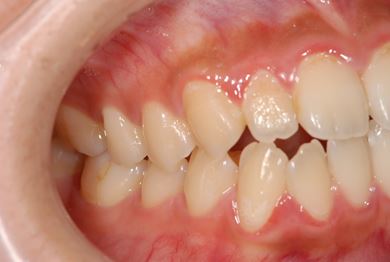

治療後

• 治療後